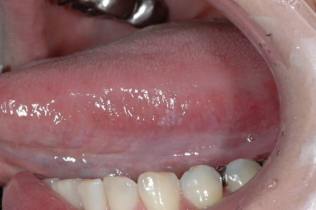

左側舌白板症 50歳代 女性

左側舌の違和感と白書病変の精査を主訴に当クリニックを受診。左側の舌に白色病変を認め白板症の臨床診断下、細胞診を施行した。細胞診の結果はClass IIであり、問題ないことをお伝えしたが、病変が小さいうちに切除を希望したため、全摘生検を行った。組織診断の結果は軽度上皮性異形成であった。その後再発等ない(費用:保険診療のみ)

初診時の口腔内所見 左側舌縁部に白色病変を認める。大きさも小さく患者さんと相談して全摘生検を施行した。